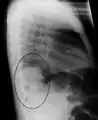

| A chest X-ray showing a very prominent wedge-shape bacterial pneumonia in the right lung | |

The discovery of x-rays made it possible to determine the anatomic type of pneumonia without direct examination of the lungs at autopsy and led to the development of a radiological classification. Early investigators distinguished between typical lobar pneumonia and atypical (e.g. Chlamydophila) or viral pneumonia using the location, distribution, and appearance of the opacities they saw on chest x-rays. Certain x-ray findings can be used to help predict the course of illness, although it is not possible to clearly determine the microbiologic cause of a pneumonia with x-rays alone.

Right upper lobe pneumonia as marked by the circle.- Left upper lobe pneumonia with a small pleural effusion.